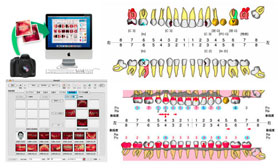

定期検診・予防歯科は担当衛生士制をとっております

衛生士専用ユニットを使用し、衛生士が定期検診・予防歯科を行います。また患者様ごとに口腔内の状態をプリント化して比較を行うことができます。

口腔内カメラを使用

術前・術後について、わかりやすい説明を心がけております。従って患者様はご自身の口腔内でどのような治療を行っているか把握できます。

術前・術後について、わかりやすい説明を心がけております。従って患者様はご自身の口腔内でどのような治療を行っているか把握できます。